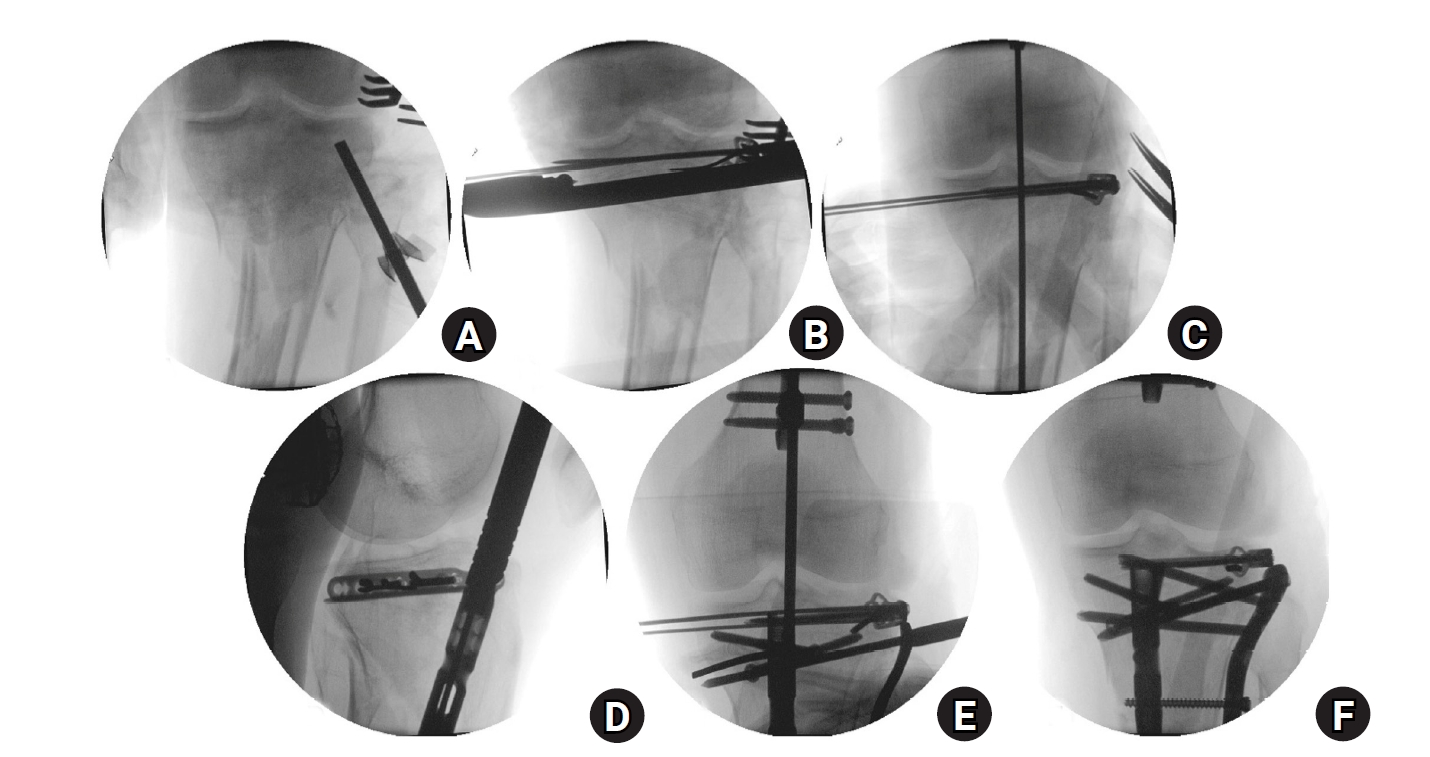

Fig. 6.

Fluoroscopic images and schematic illustrations of the rim plate-assisted intramedullary nail and plate combination technique. (A) Lateral plateau depression was elevated. (B, C) A contoured 2.7-mm variable-angle locking compression plate was applied with medial-to-lateral compression and fixed to unify the plateau into a single segment. (D) Intramedullary nailing was performed via the suprapatellar approach. (E) Alignment was confirmed with a rod. (F) A 4.5-mm proximal lateral tibia plate was added for final fixation.

Surgical technique

As in case 1, the procedure started with converting the tibial plateau fracture into a single segment using a rim plate. An anterolateral approach was chosen because of the anterolateral location of the main fracture. The patient had a lateral condylar depression of the tibial plateau, which was initially elevated using an impactor (Fig. 6A). After the elevation of the depressed fragment, Kirschner wires were temporarily fixed through the inside-out technique [9]. A 2.7-mm VA-LCP was then shaped and positioned, followed by medial-to-lateral compression using a colinear clamp (Fig. 6B). Both cortical and locking screws were inserted through the VA-LCP, which connected the plateau fragments into a single segment (Fig. 6C). A suprapatellar approach was employed for IM nailing (Fig. 6D). As in case 1, only three cancellous screws could be inserted into the proximal fragment through the IM nail. To enable immediate full weight bearing, an additional plate was applied to augment fixation, which completed the NPC technique (Fig. 6F). In this patient, the longest available 4.5-mm LCP proximal tibia plate did not provide sufficient construct length. Therefore, a 4.5-mm LCP proximal lateral tibia plate was used instead; this plate has a proximally oblique design, in contrast to the sharply angled, inverted “L”-shaped design of the standard proximal tibia plate. Postoperative plain radiographs and CT images are shown in Fig. 7.